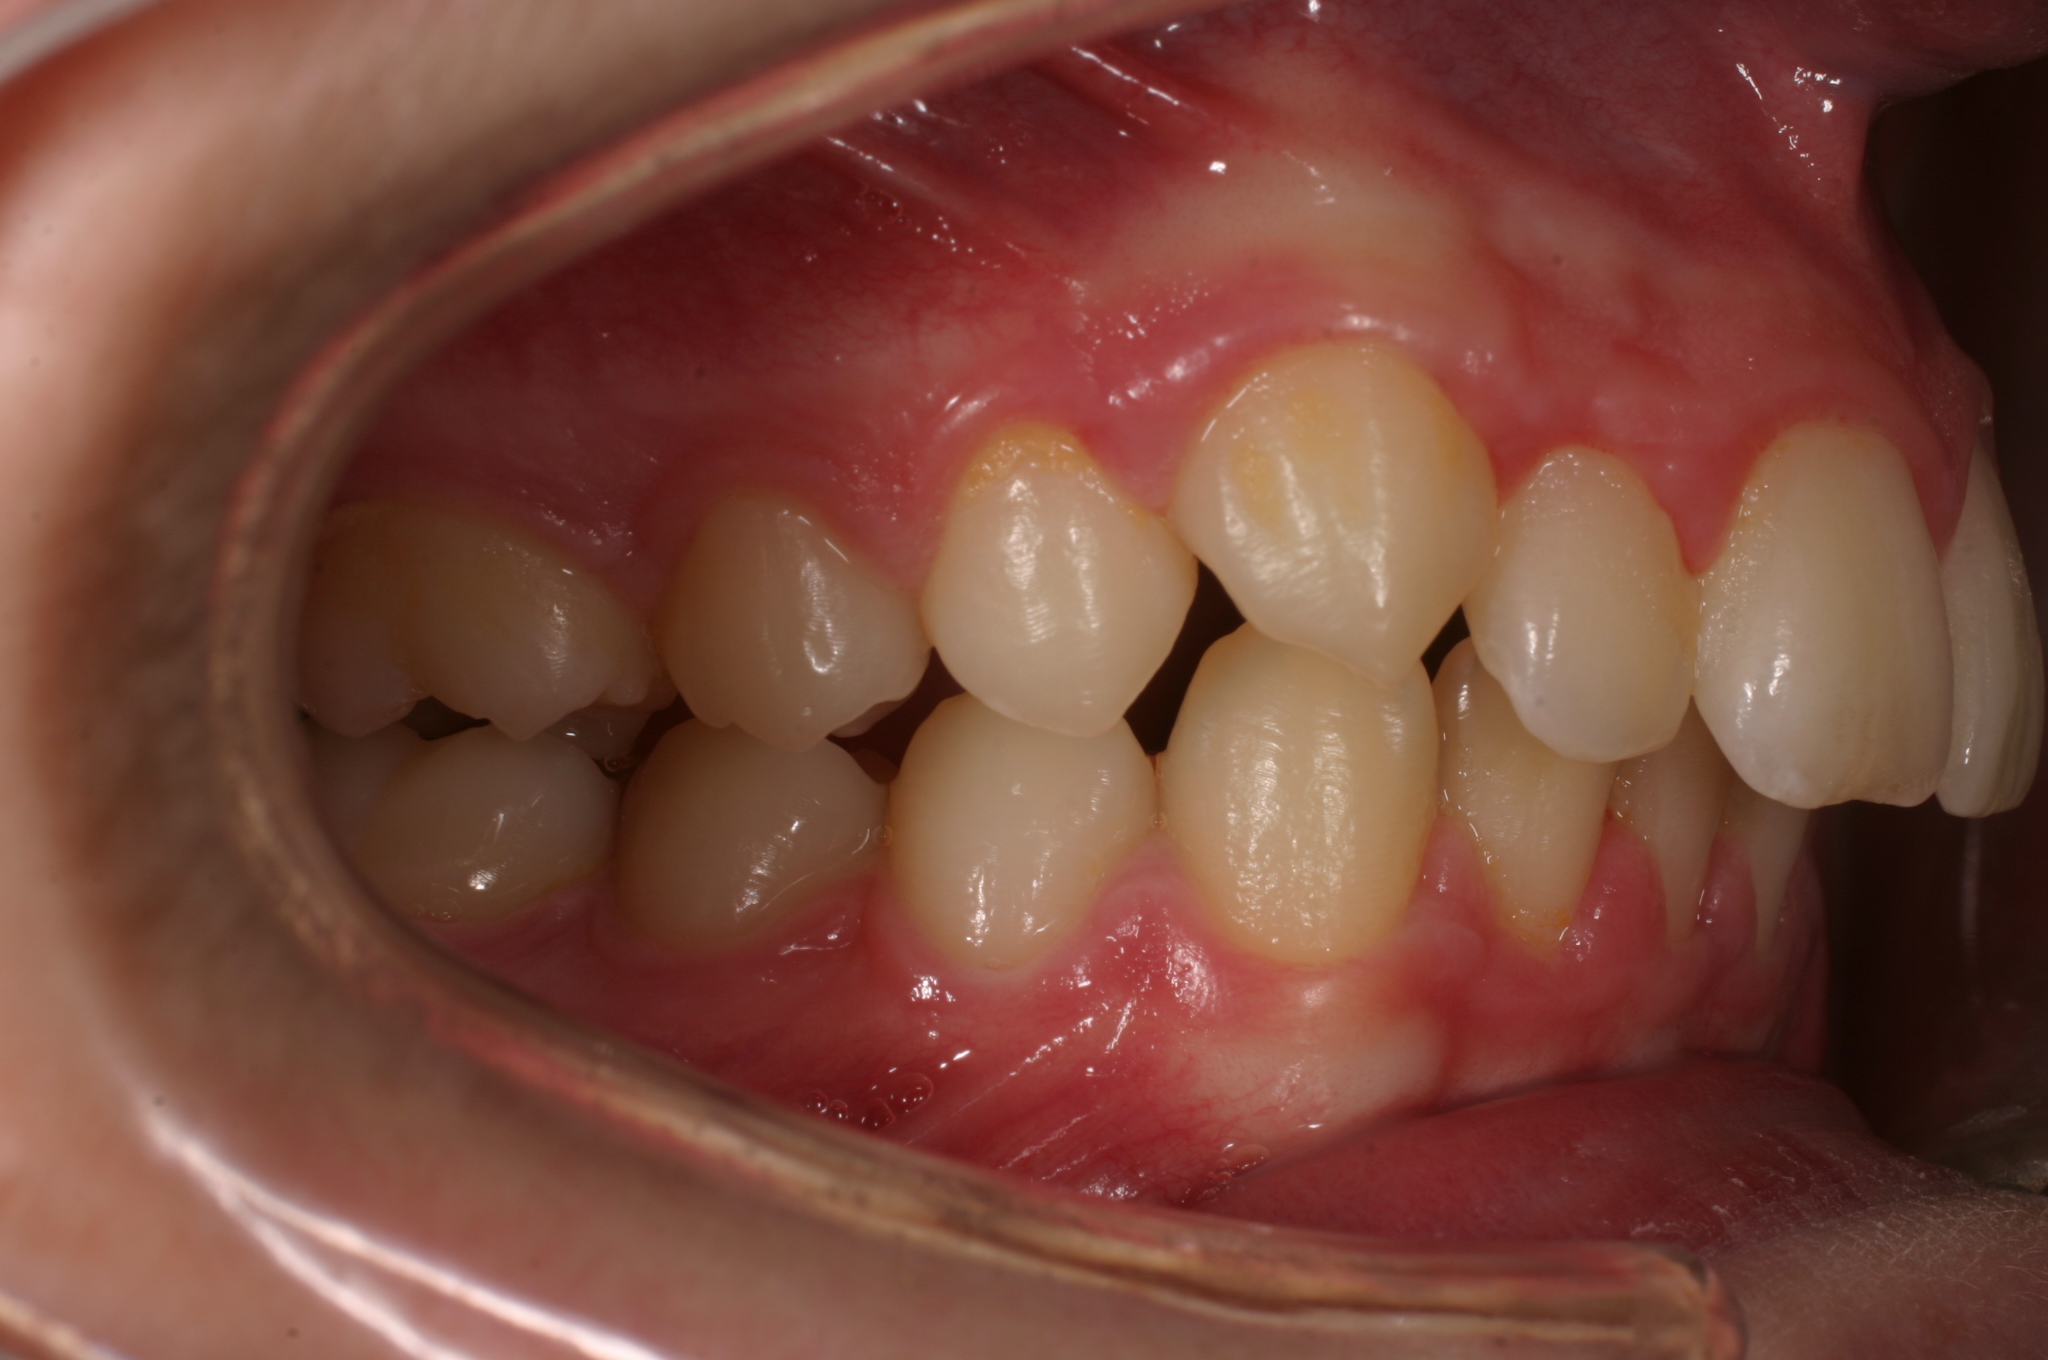

Ho ricevuto domande specifiche circa le caratteristiche di un odontoma! Questa e' un malformazione benigna che puo' avere diverse forme (semplice, composta e complessa)e varia grandezza!In questo caso ancora in trattamento, viene mostrato l'odontoma che impedisce al canino di erompere, la chirurgia di rimozione eseguita in anestesia locale con la collaborazione della Dott.ssa Laura Marchione, l'odontoma con i suoi componenti e la trazione del canino! Aggiungo le foto a trattamento quasi completato! Alla fine potete osservare le foto iniziali del trattamento! In effetti il caso era una II classe scheletrica trattata prima con Twin-Block e poi successivamente con fissa e chirurgia!